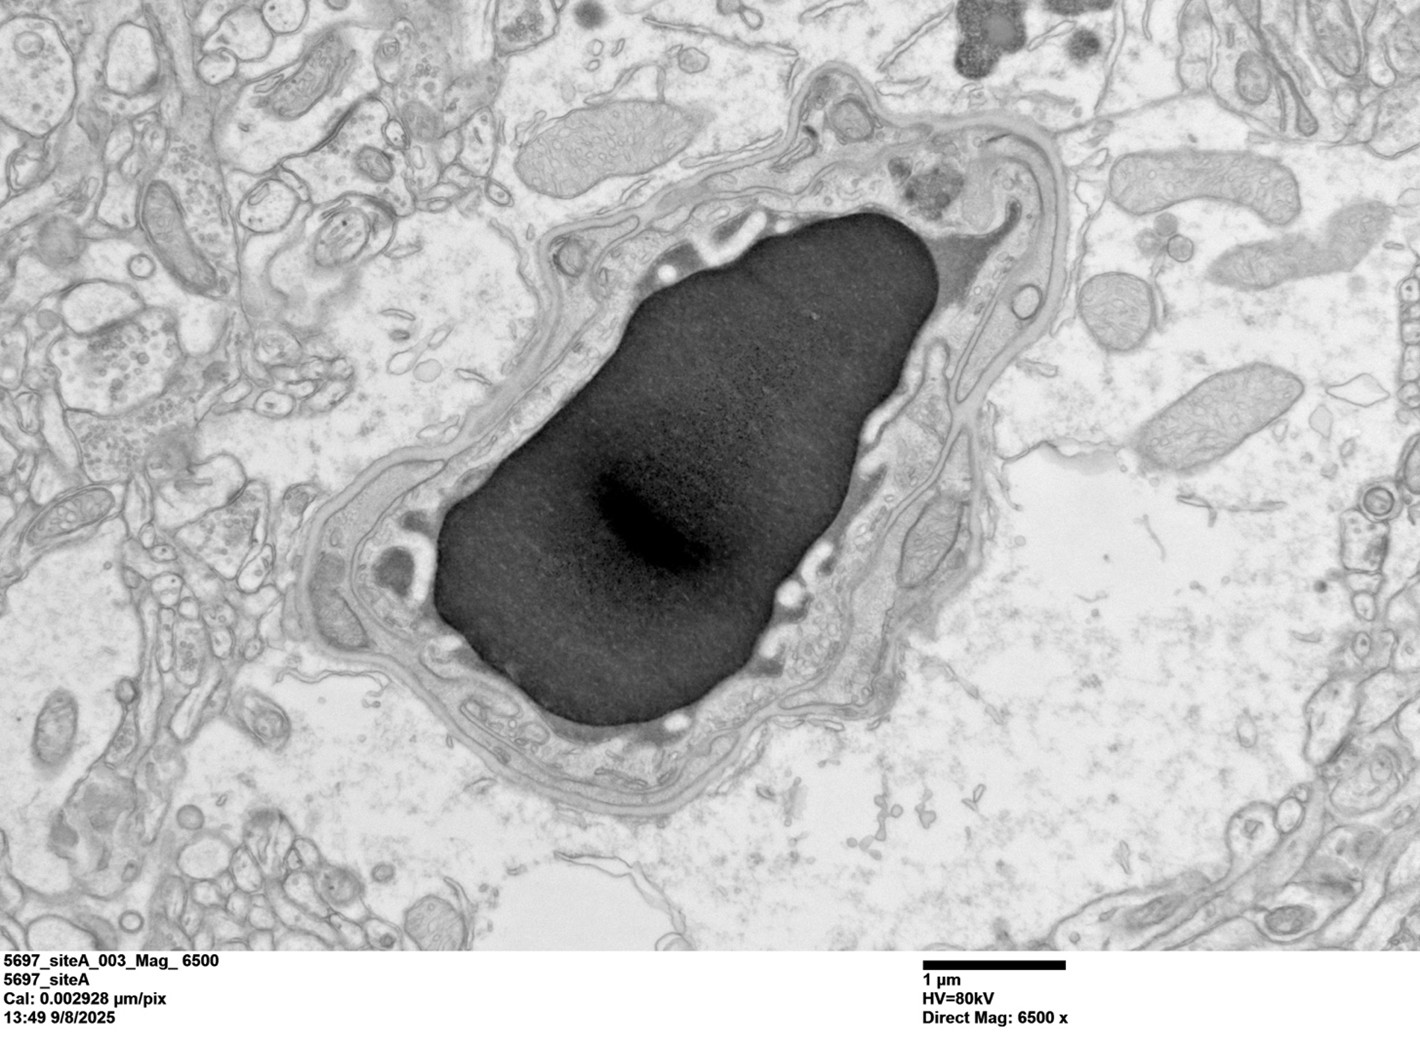

Lucy’s TEM Image of a Cortical Capillary from a WT mouse brain, imaged with the JEM-120i

Pictured: The capillary lumen contains a red blood cell (darker signal) that is surrounded by an electron-dense tracer. The endothelial cell forms a very thin barrier around the lumen and is enclosed by the basement membrane, with pericyte processes embedded within it. The entire vessel is surrounded by astrocytic endfeet, visible as a lighter, translucent layer. Notably, the tracer is halted at the endothelial tight junction (right side of the endothelial cell) and does not penetrate the basement membrane, illustrating an intact and functional blood–brain barrier.

Lucy’s research focuses on understanding how the BBB maintains, and sometimes loses, its integrity at the cellular and subcellular levels: “I study how endothelial cells regulate vesicle trafficking and membrane dynamics, and how these processes affect BBB function in health and disease.” To do this, Lucy combines molecular genetics, in vivo mouse models, and advanced imaging approaches to visualize endothelial structures at a high resolution.

Using the JEM-120i, Lucy can observe ultrastructural features at a level of clarity and confidence to interpret what is occurring at the cellular and subcellular levels. “The JEM-120i is incredibly reliable for rapid screening and high-contrast visualization of endothelial ultrastructure” Lucy explains. “For me, the greatest strength is clarity: tight junctions, vesicles, basement membrane contours – everything is crisp, clean, and interpretable.” The importance of these images? “Every image carries the possibility of changing how we think about the BBB.”

The best part of the process? Visualizing how the BBB becomes dysfunctional. For Lucy, these moments are unforgettable: “A disrupted junction, an unexpected vesicle population, or a membrane that suddenly tells a different story. It feels like witnessing biology reveal its secrets in real time.”